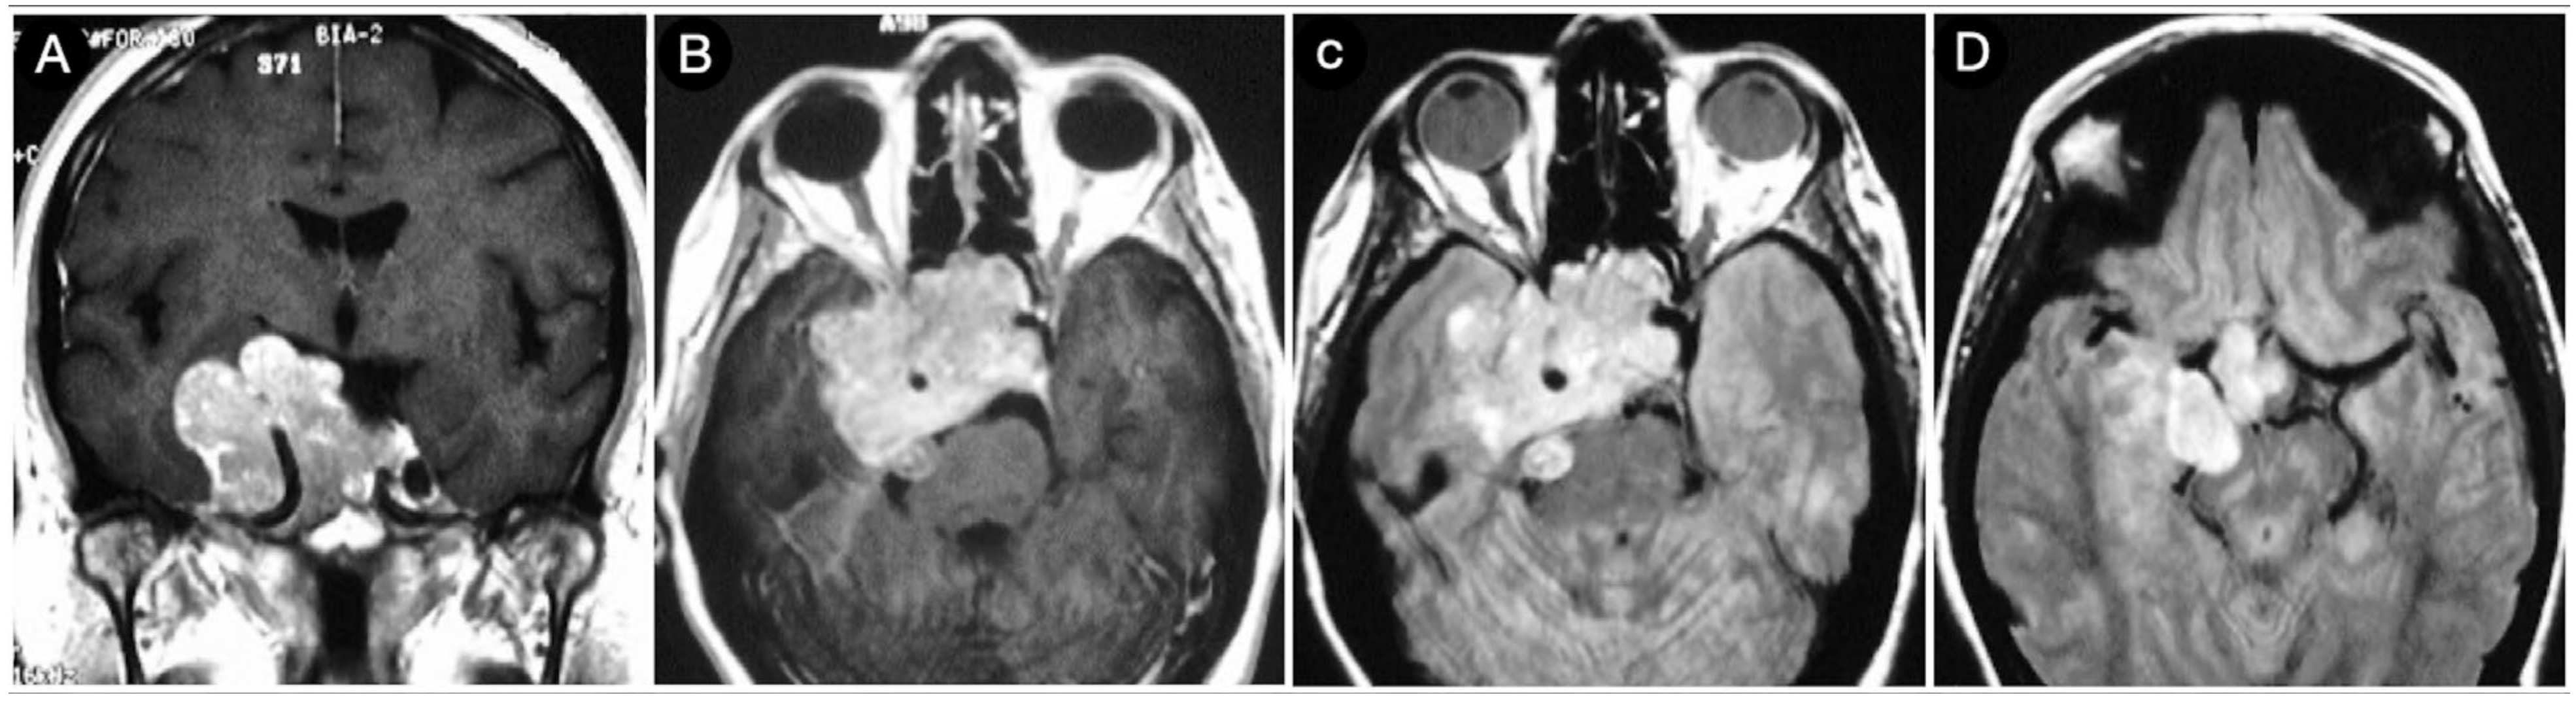

3.3.2. Case #5: Extension beyond the Lateral Wall of the Cavernous Sinus